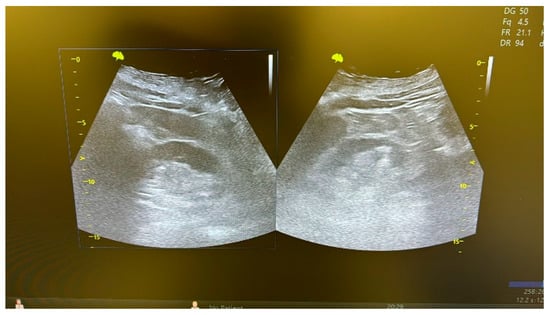

The double-J stent was removed 6 months postoperatively, following an endoscopic evaluation of the reconstructed ureter (Figure 10). At the 6-month follow-up, a CT scan or abdominal ultrasound (Figure 11) was performed to confirm the absence of stricture recurrence and normal ipsilateral renal function.

Table 1 summarizes the demographic and preoperative clinical characteristics of the patients. The minimally invasive approach was technically feasible in all patients, without needing conversion. The mean length of the ureteral stricture was 19 mm (range: 5–40 mm), calculated using the CT scan. Intraoperative and postoperative data are presented in Table 2. The median operating room time was 105 min, and the median hospital stay was 4 days. The median catheterization time and hospital stay were similar in all patients, and no significant preoperative complications occurred. The double-J stent was removed at 6 months after surgery, after an endoscopic evaluation of the procedure (Figure 10). A CT scan or an abdominal ultrasound (Figure 11) was performed 6 months later to confirm the absence of stricture recurrence and normal ipsilateral renal function. All patients remained symptom-free during the 38-month clinical follow-up.

Figure 11. Ultrasound evaluation of the kidneys during follow-up.